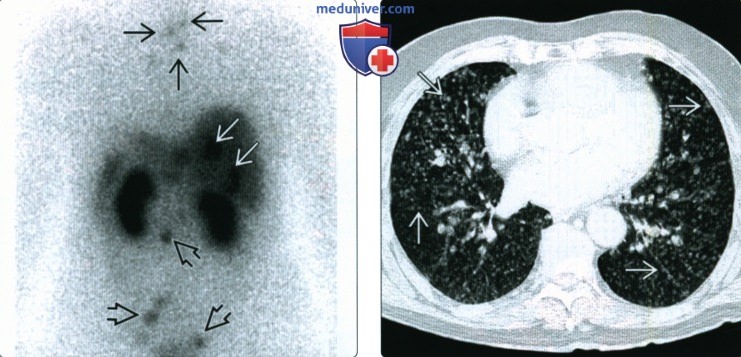

Фотографии опухоли медуллярной аденокарциномы